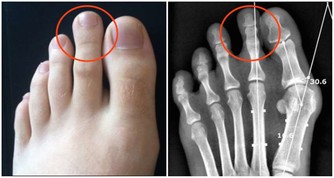

3、骨關節炎---最常見的關節病。

是軟骨磨損導致的關節病,主要表現為關節疼痛,稍活動後減輕,過度活動後又加重。治療是吃非甾體類抗炎藥、鍛鍊和減肥,一般不用手術治療。 但風濕性關節炎患者的關節軟骨破壞較嚴重的,需要做膝關節置換術。